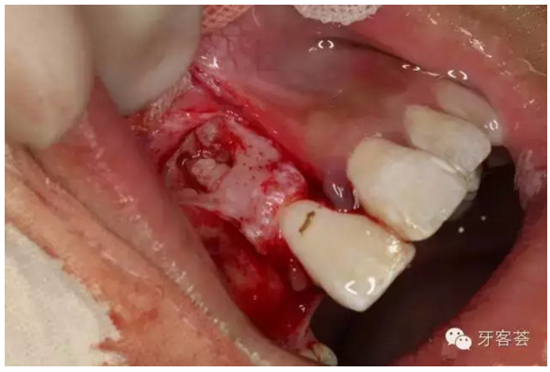

圖9:清理12牙槽窩

圖10:清理完成的12牙槽窩,并翻瓣暴露11的根尖區(qū)骨壁,骨壁完整、無破壞。